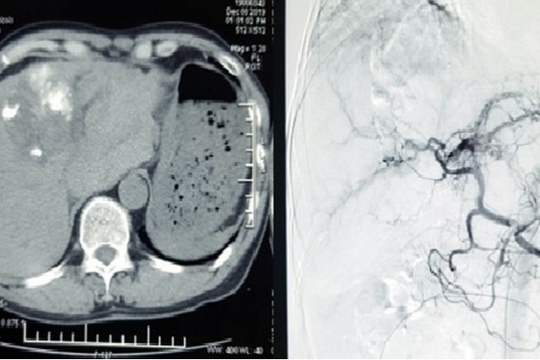

Nam thanh niên 20 tuổi gặp tai nạn giao thông vỡ gan nguy kịch được cứu sống nhờ phương pháp này

GĐXH – Bệnh nhân bị chấn thương gan độ IV, ổ chảy máu hoạt động, gãy đa xương sườn bên phải, tràn khí, tràn dịch màng phổi phải.